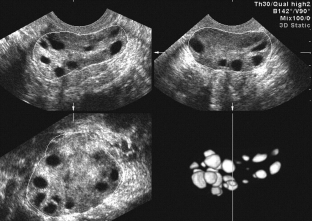

In all forms, the concentration of freely circulating testosterone increases, as directly indicated by the severity of hirsutism. An important point in the diagnosis is the determination of insulin and blood glucose. For polycystic ovaries, the value of the index of the ratio of glucose to insulin is more than 3. A very highly informative method is transvaginal ultrasound of the ovaries.

Ultrasound criteria for polycystic ovary syndrome

- increase in ovarian volume (up to 20 cm³);

- ovarian stromal hyperplasia (25% of volume);

- the presence of more than 10 atretic follicles, located on the periphery and covered with a thickened capsule.